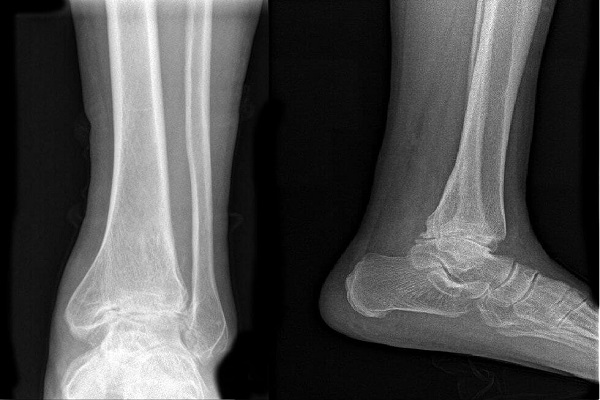

Fractura de Tobillo